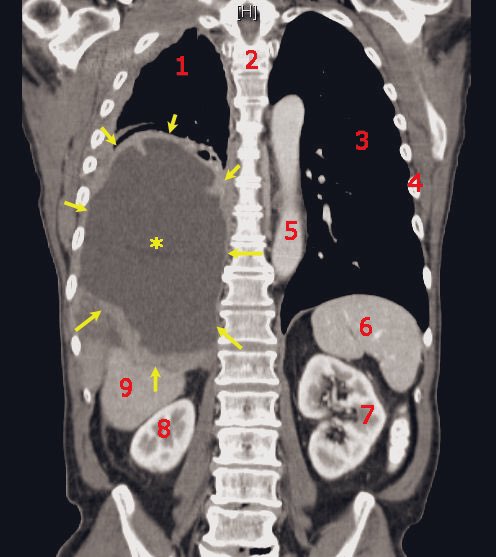

حصى الكلى

تسبب الحصوات الكلوية آلاماً حادة في المجاري البولية، تجعل المريض يئن ويصرخ من شدة الألم، وتحتاج إلى عمل جراحي لإخراجها.